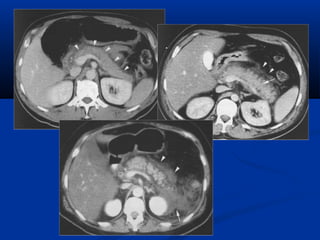

TRÒ SOÁ ÑAÄMÑOÄ Moãi phaân töû vaät (Voxel) coù trò soá töông öùng vôùi möùc ñoä haáp thu tia cuûa moâ vaø ñöôïc bieåu thò baèng caùc ñoä xaùm khaùc nhau treân hình ôû töøng phaân töû aûnh (pixel).

TRÒ SOÁ ÑAÄMÑOÄ Ñaäm ñoä cuûa nöôùc : 0 ñôn vò Hounsfield (HU) Ñaäm ñoä cuûa xöông :+ 1000 HU Ñaäm ñoä cuûa khí :–1000 HU Ñaäm ñoä môõ :–100 HU (ROI : Region Of Interest)

Một số mậtđộ (HU)Một số mật độ (HU)

Loaïi moâ Tròsoå chuaån (HU) Trò soá giôùi haïn (HU) Xöông ñaëc 250 >   Gan 65 +/– 5 45 – 75 Cô 45 +/– 5 35 – 50 Laùch 45 +/– 5 40 – 60 Haïch 45 +/– 10 25 – 55 Tuïy taïng 45 +/– 10 20 –40 Thaän 40 +/–10 Môõ - 65 +/–10   - 80 – - 100

THAY ÑOÅI HÌNHAÛNH -Trò soá ñaäm ñoä cuûa caùc moâ cô theå thay ñoåi töø –1000HU ñeán +1000 HU -Bieåu hieän treân hình baèng caùc ñoä xaùm khaùc nhau. -Tuy nhieân maét thöôøng cuûa chuùng ta chæ phaân bieät ñöôïc töø 15 – 20 ñoä xaùm khaùc nhau. Do ñoù ñeå coù theå phaân bieät ñöôïc caùc caáu truùc khaùc nhau ñaët cöûa soå (Window setting ) taïo töông phaûn giuùp maét thöôøng ta nhaän bieát ñöôïc.

ÑOÄ ROÄNG CÖÛASOÅ (WINDOW WIDTH) -Giôùi haïn treân vaø giôùi haïn döôùi cuûa trò soá ñaäm ñoä caàn khaûo saùt . - Trò soá ñaäm ñoä ngoaøi giôùi haïn treân seõ coù maøu traéng treân hình, caùc trò soá ñaäm ñoä

TRUNG TAÂM CÖÛASOÅ ( WINDOW LEVEL ) Trò soá giöõa cuûa ñoä roäng cöõa soå Ñieàu chænh cho phuø hôïp vôùi toå chöùc moâ caàn khaûo saùt